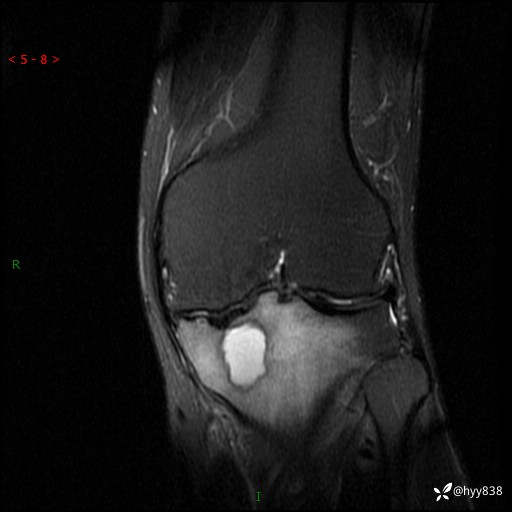

cor T2WIfs